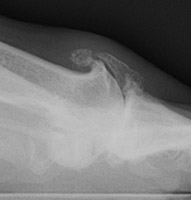

Osteoarthritis: Lateral View - Large dorsal osteophytes at 1st MTP jointOsteoarthritis: AP View - Large osteophytes and joint space narrowing at 1st MTP jointOSTEOARTHRITIS non-inflammatory deterioration of articular cartilage with articular surface and marginal bone formation.

Radiographic manifestations may include marginal osteophyte and subchondral bony cyst formation, eburnation, and interosseous joint space narrowing. First metatarsal phalangeal joint osteoarthritis is frequently associated with hallux valgus deformities. Calcaneal spurs, when manifested, are sharp and well defined.